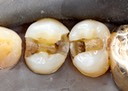

Joe Cha #20 amalgam removal